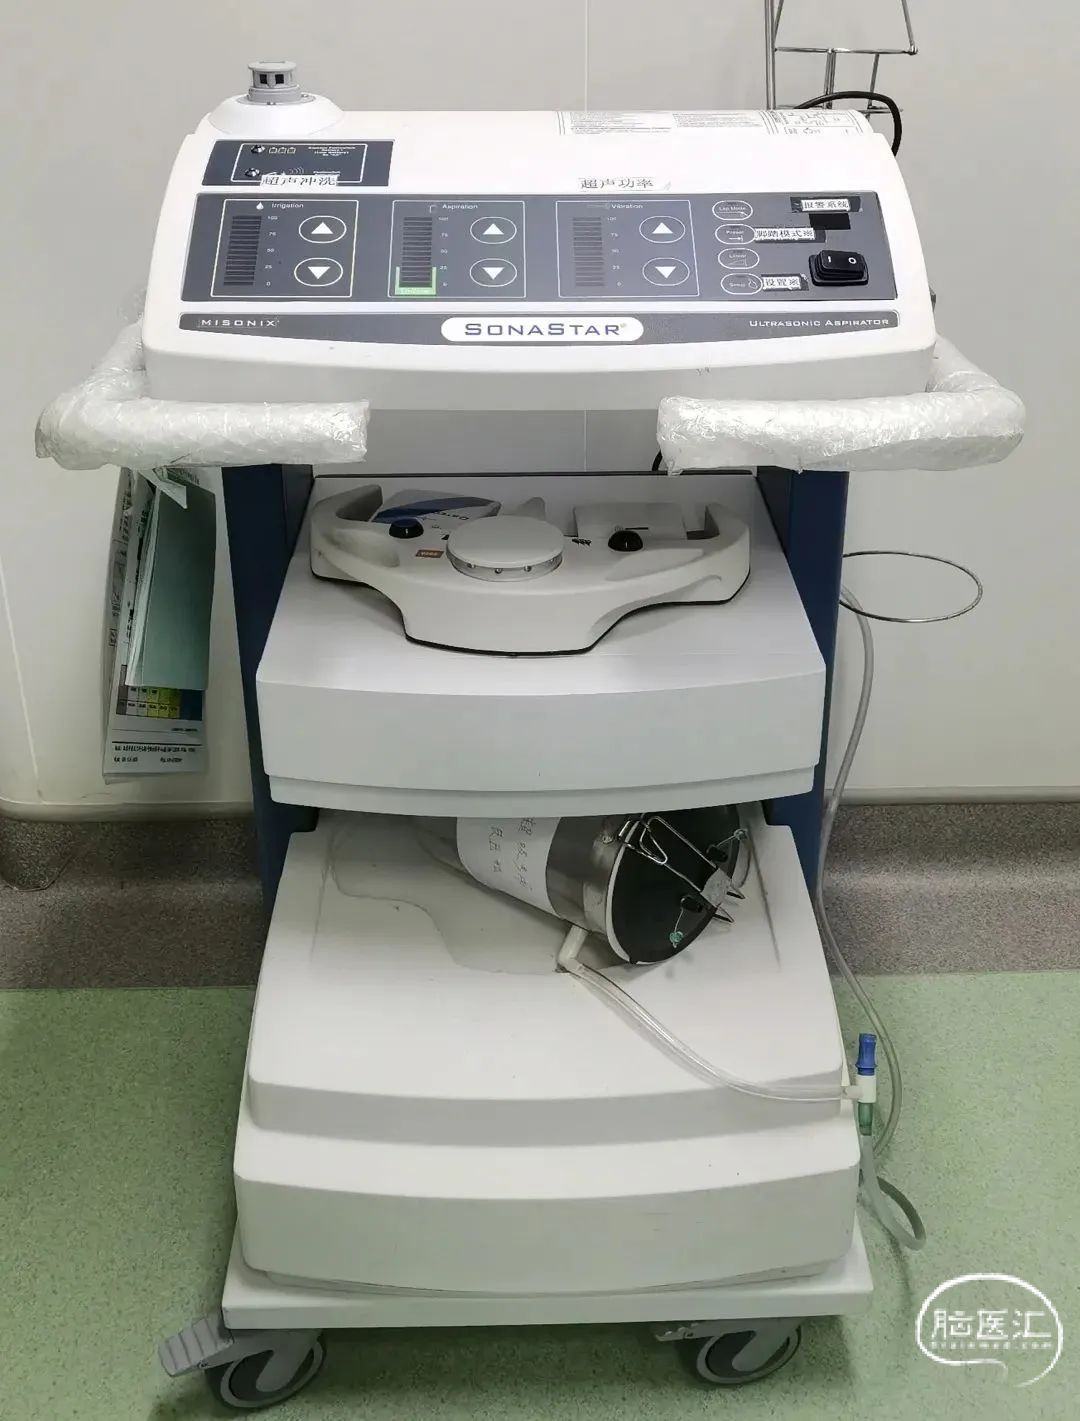

SonaStar FS-1000-RF

超声外科吸引系统